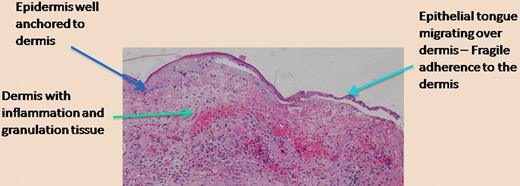

This type of work, while focused on a rare genetic disease that results in mechanical skin fragility and difficult-to-heal wounds, has ramifications for other aspects of tissue integrity and wound healing. A delicate balance exists between anchoring of epithelia (like in skin) to underlying structures, the necessity for cells to migrate upon tissue injury, and the traction required for a more “temporary” anchoring of cells as they migrate.7 The figure is offered as a telling histologic photomicrograph of a chronic wound in which the epidermis is finally migrating over the underlying dermis. As shown on the left side of the figure, away from the wound where the epidermis is thicker, one can expect that the anchoring of the epidermis to the dermis, for example, through type VII collagen, is strong. However, as the epidermis migrates, the keratinocytes need to free themselves from the hemidesmosomes and the structural proteins (including laminin-332, type VII collagen) that are so vital for tissue integrity. We believe that, given the emerging role of bone marrow cells in wound healing, we may ultimately be able to manipulate the contribution of specific marrow cells and alter this delicate balance as required.

Epidermal migration over a chronic wound. The photomicrograph shows the histology of a chronic wound in which the epidermis migrates over the inflamed and vascular dermis. The separation of the epithelial tongue from the underlying dermis is an artifact from tissue preparation, but it properly suggests that the anchoring is diminished in order to allow keratinocyte migration to occur. (H&E; ×200.)

Epidermal migration over a chronic wound. The photomicrograph shows the histology of a chronic wound in which the epidermis migrates over the inflamed and vascular dermis. The separation of the epithelial tongue from the underlying dermis is an artifact from tissue preparation, but it properly suggests that the anchoring is diminished in order to allow keratinocyte migration to occur. (H&E; ×200.)